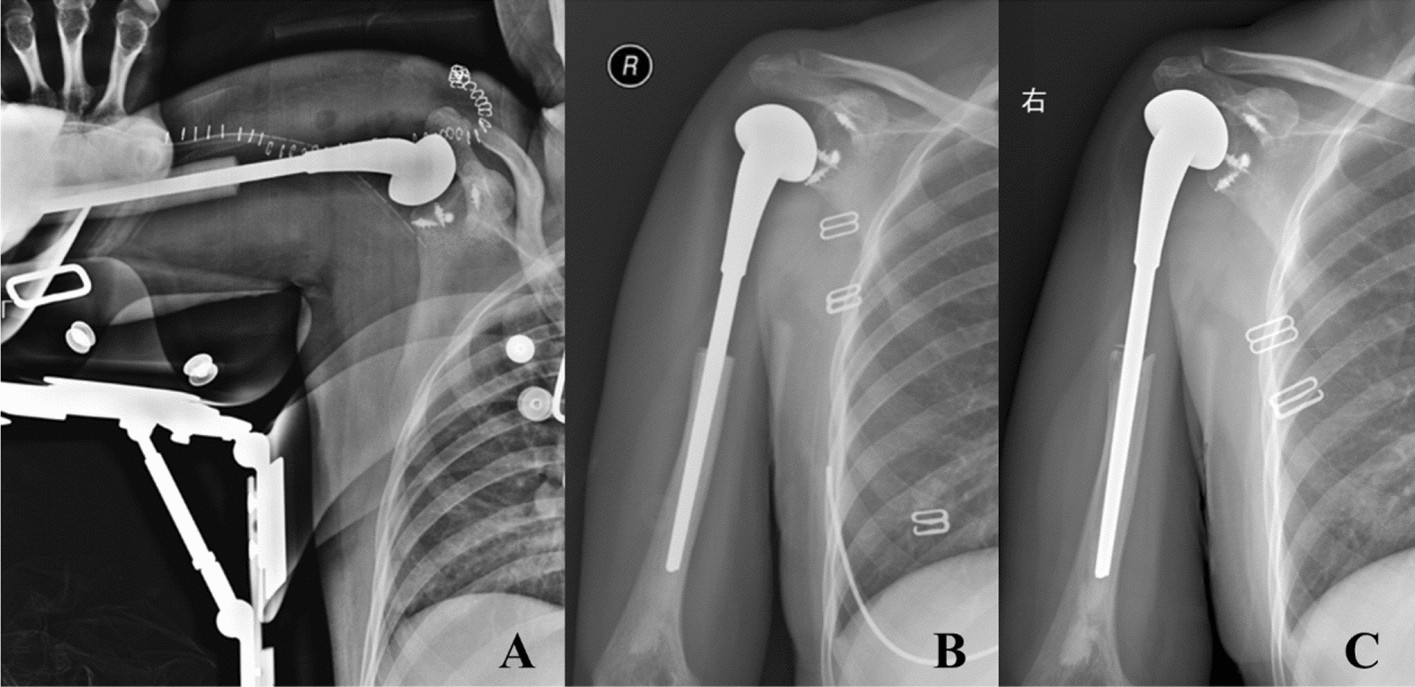

Figure 3

The postoperative radiography (A) showed 4 anchors were fixed in different directions (upper, lower, front and back) of the glenoid to restore the stability of the prosthesis. The radiography 3 months postoperative (B) and the radiography 104 months postoperative (C) showed the prosthesis was in stable position without obvious loosening and dislocation.